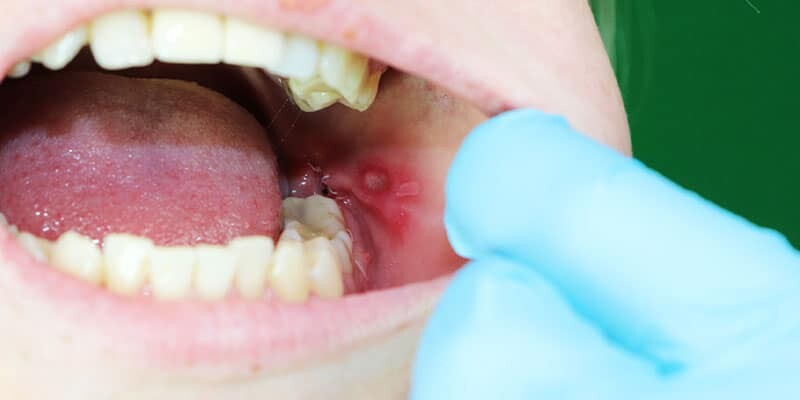

Mouth ulcers

Mouth ulcers, also known as canker sores, are small painful lesions that can appear on the lips, gums, tongue, or inside the cheeks. They are often caused by stress, irritation, or viral infections. To relieve pain and promote healing, rinse your mouth with a saline solution and avoid spicy or acidic foods. If ulcers persist for more than two weeks, it is advisable to seek medical attention.